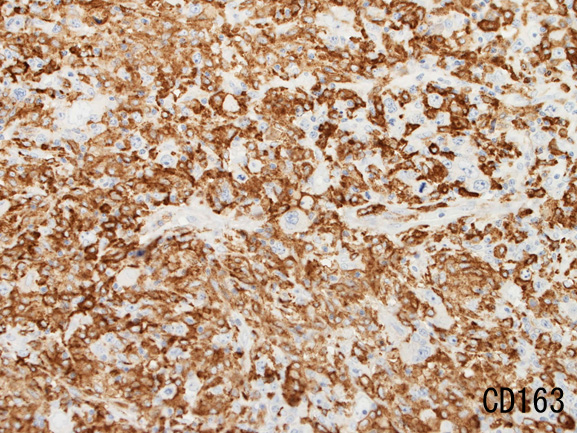

背景細胞はCD3+ Tリンパ球(CD8>CD4)とCD163, CD68陽性組織球。

| MUM-1 | CD3 | 背景組織球はCD163+ | |